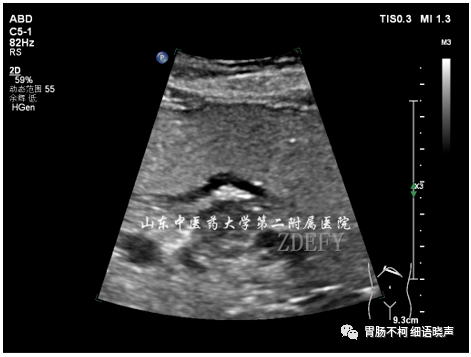

病例三,胃体偏后壁胃壁增厚性病变,层次尚清晰,黏膜面浅溃疡形成: